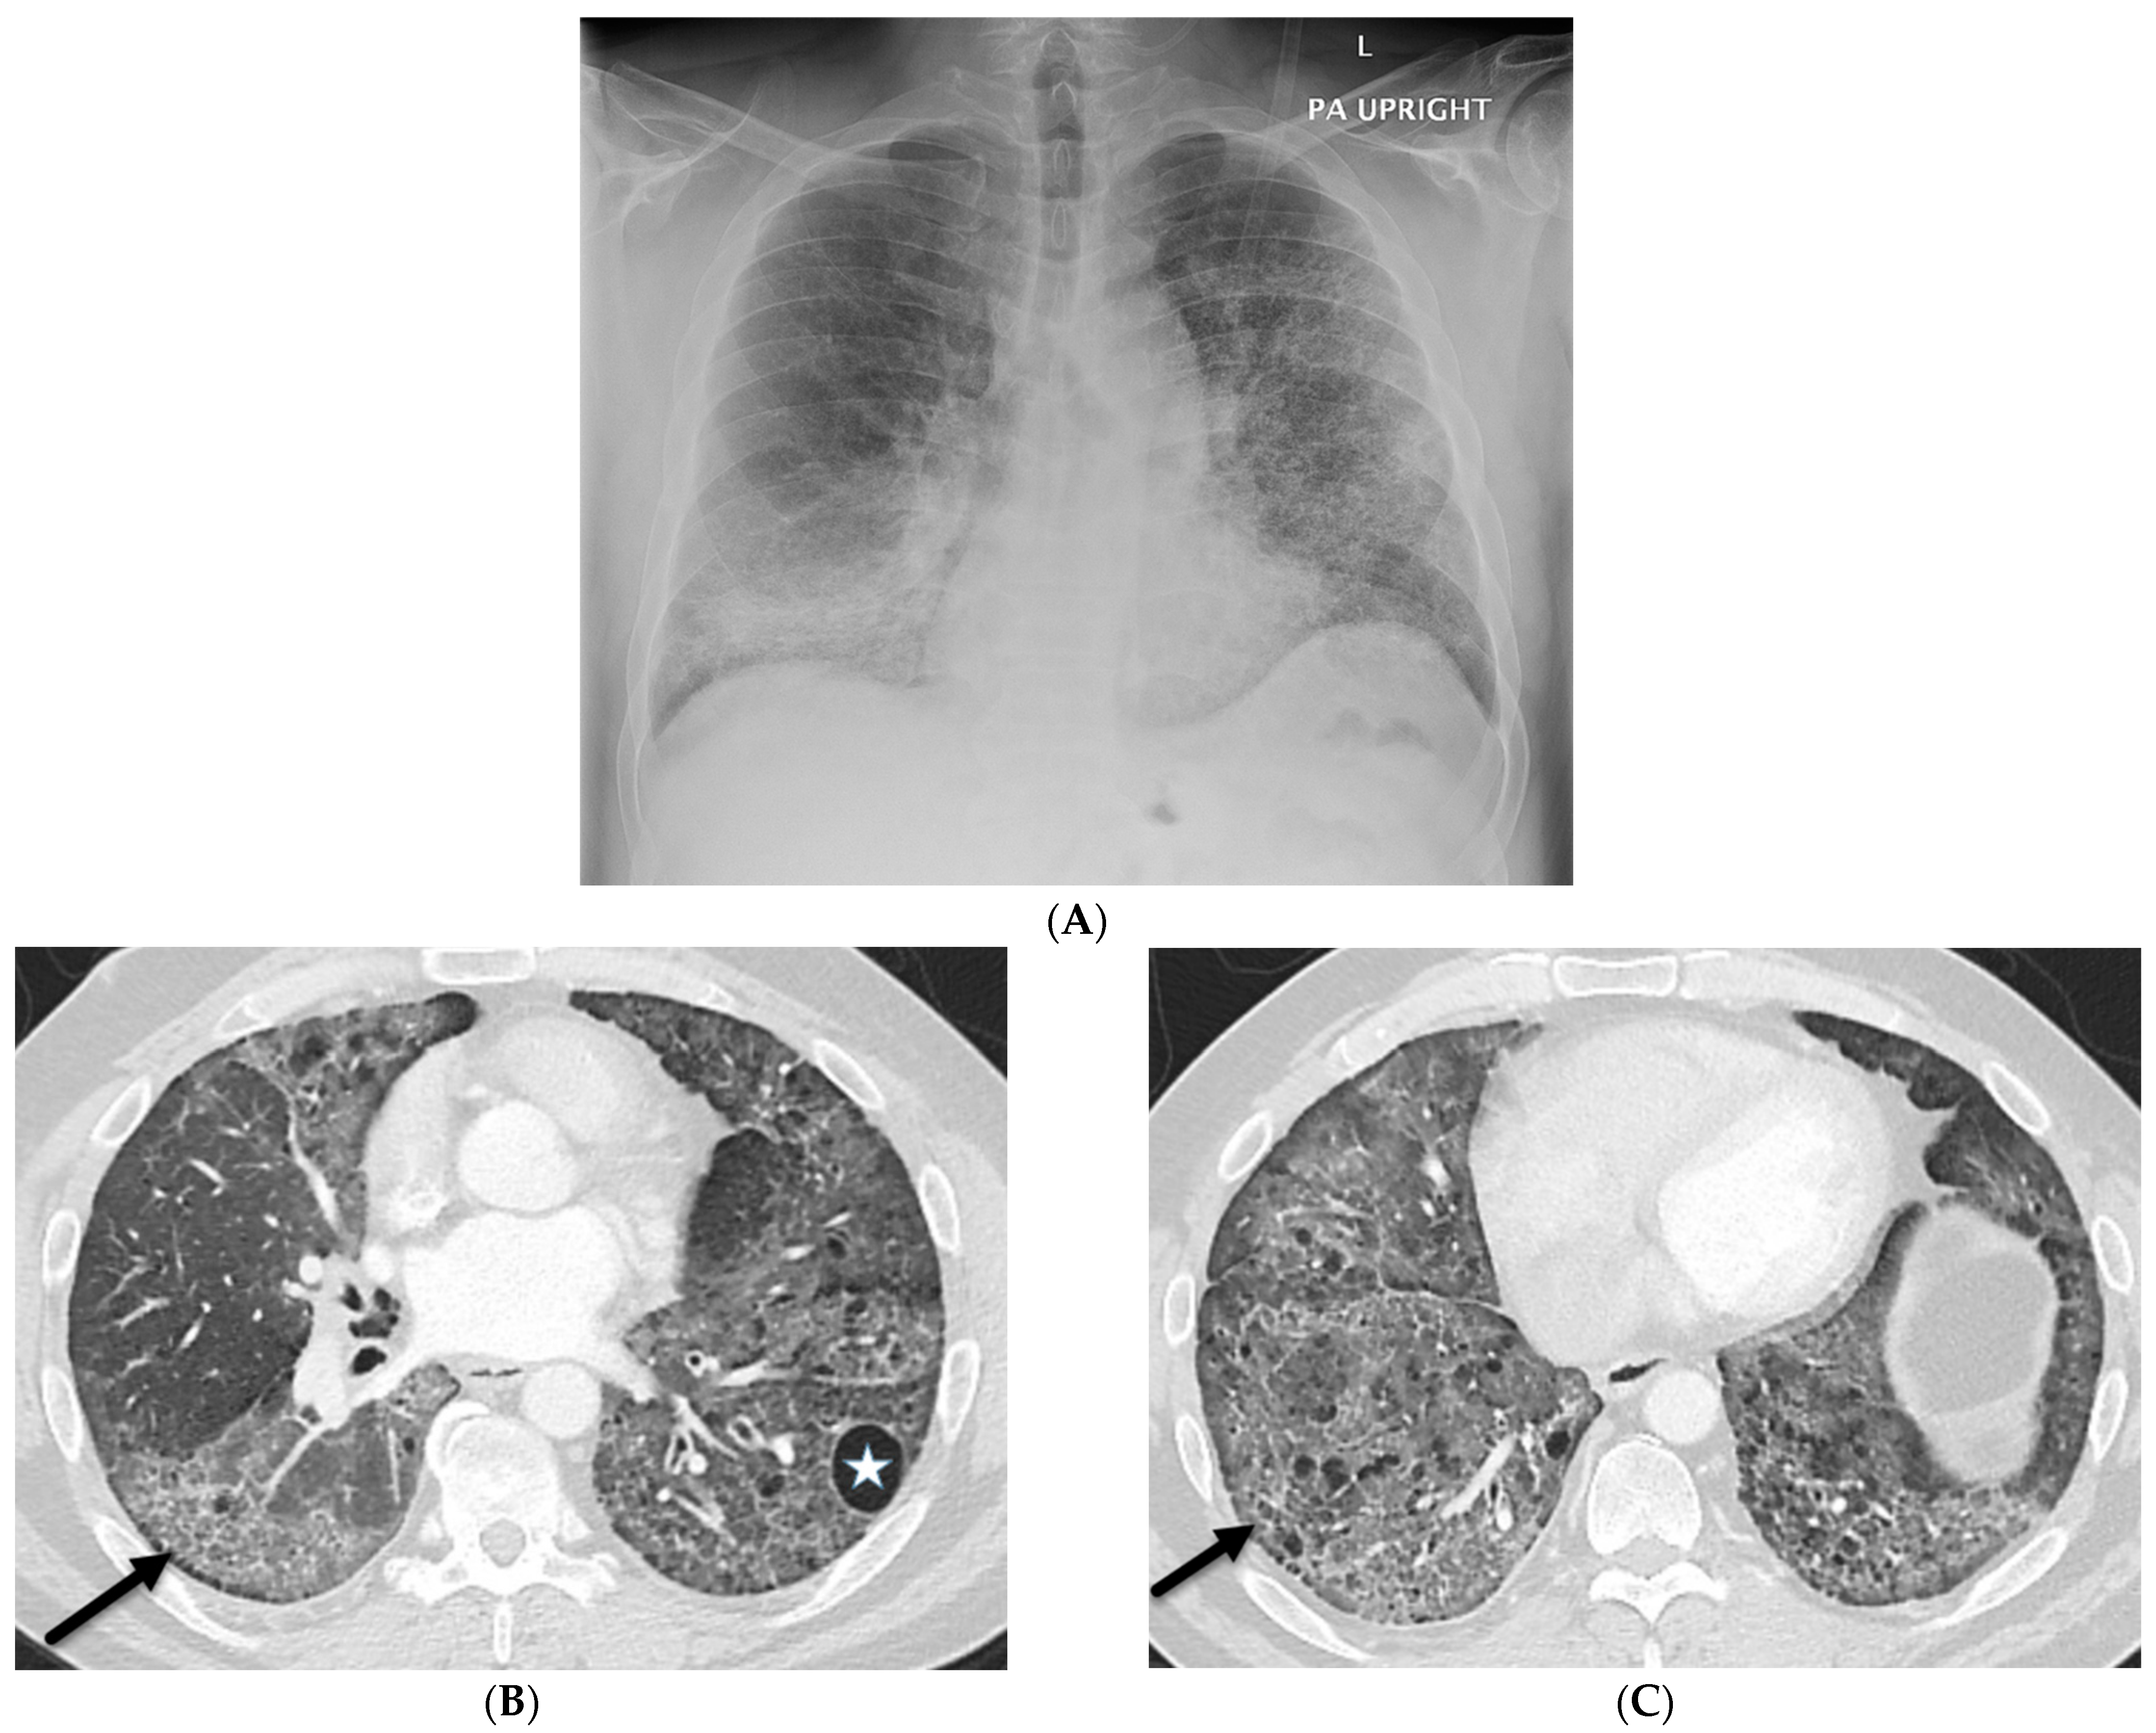

4.1. Lipoid Pneumonia

4.7. Pulmonary Vein Stenosis (PVS)

5.2. Kaposi’s Sarcoma